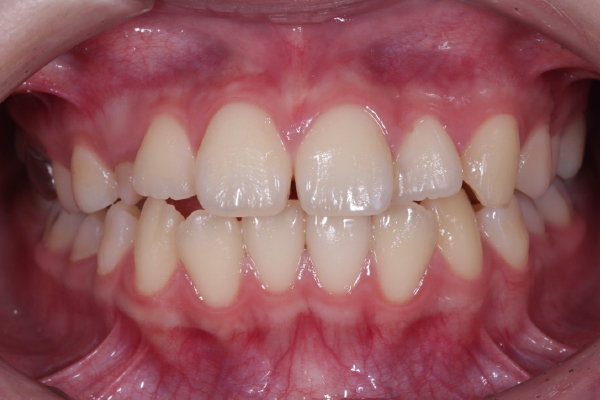

右上の乳犬歯が長期間残っていることを気にされ来院されました。

歯並び自体の大きな乱れはありませんでしたが、永久歯(犬歯)が萌出していない状態を心配され、精密検査を希望されました。

検査の結果、上顎犬歯が顎骨内に埋伏していることを確認しました。

自然萌出は困難と判断し、矯正治療による牽引で歯列内へ誘導する治療を計画しました。

AFTER

本症例では適切なタイミングで診断と介入を行えたことで、矯正的牽引により永久犬歯を歯列内へ誘導することができました。

犬歯は咬合誘導および審美性に重要な役割を担う歯であり、早期の診断が将来的な咬合安定につながります。

今後は保定管理および定期的な経過観察を行っていきます。